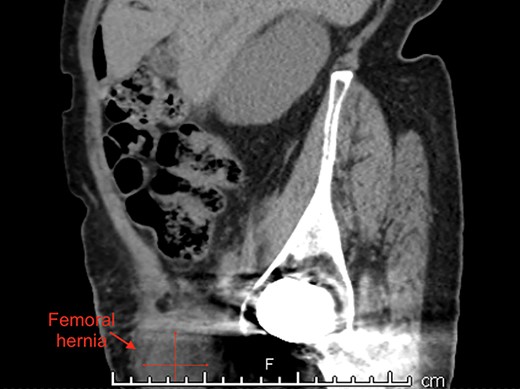

An 87-year-old Caucasian female presented to the emergency department with a 5-day history of worsening right groin pain, with an associated 2-day history of generalized malaise and fatigue. She denied fever, nausea and vomiting or signs of bowel obstruction. Her past medical history included previous right total hip replacement, type 2 diabetes mellitus and chronic renal impairment. Her vitals were normal, and examination revealed a tender right groin lump below the level of the pubic tubercle approximately 4 × 4 cm in size, with overlying erythematous skin changes. Biochemical investigation revealed a normal white cell count of 10.0 × 109/L and neutrophil profile of 7.8 × 109/L but an elevated C-reactive protein (CRP) of 190 mg/L. Contrast-enhanced computed tomography (CT) scan revealed a hypodense rounded lesion measuring 3.8 × 4.3 × 3.1 cm, medial to the right femoral vessels and extending lateral to and below the level of the pubic tubercle in the proximal anterior thigh, most consistent with a incarcerated femoral hernia (Figs. 1–3). The presence of right total hip replacement artifacts precluded accurate assessment for communication of the lesion with the peritoneal cavity.

Axial view of right femoral hernia, note the significant image distortion from the right total hip replacement beam artifacts.